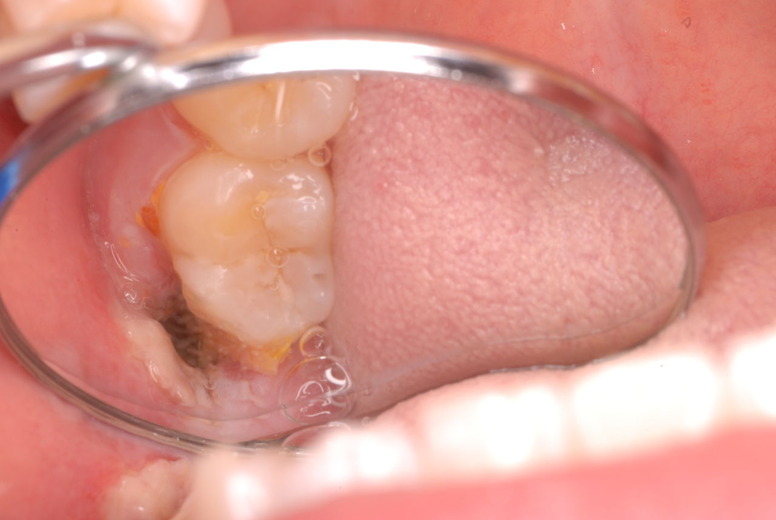

写真左下の親知らずが痛くなり抜歯しました。その後歯茎を除去して虫歯を露出させる処置を二回ほどしています。

レントゲンでは小さいですが、こう言う虫歯が一番怖いのです。

治療の成功率は極めて悪くすぐ再発しやすいのです。